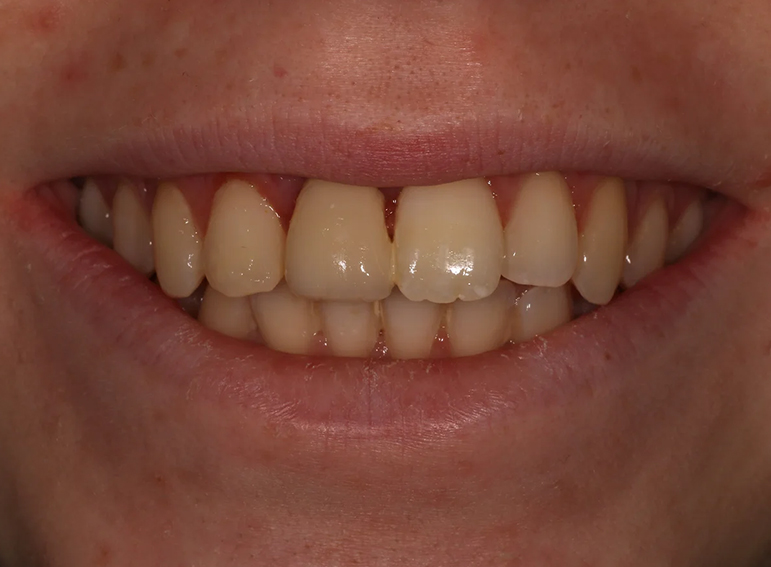

Gingival surgery and composite build up of an UR2 to resemble an UR1 following orthodontic treatment.